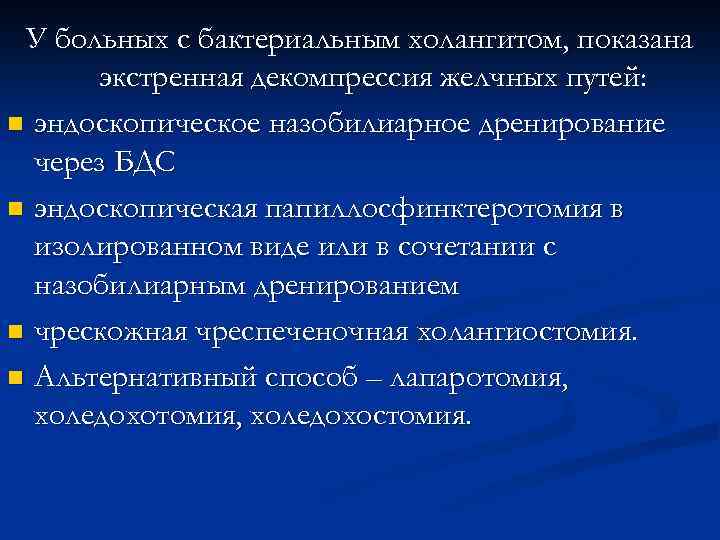

У больных с бактериальным холангитом, показана экстренная декомпрессия желчных путей: n эндоскопическое назобилиарное дренирование через БДС n эндоскопическая папиллосфинктеротомия в изолированном виде или в сочетании с назобилиарным дренированием n чрескожная чреспеченочная холангиостомия. n Альтернативный способ – лапаротомия, холедохостомия.

У больных с бактериальным холангитом, показана экстренная декомпрессия желчных путей: n эндоскопическое назобилиарное дренирование через БДС n эндоскопическая папиллосфинктеротомия в изолированном виде или в сочетании с назобилиарным дренированием n чрескожная чреспеченочная холангиостомия. n Альтернативный способ – лапаротомия, холедохостомия.